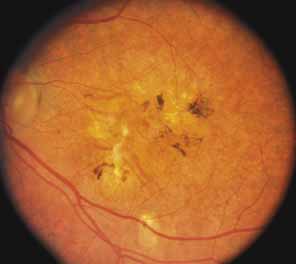

Choroideremia (gene symbol CHM; MIM No. 303100) is an X-linked disorder that is characterized by the onset of night blindness in the first or second decade of life followed by slowly progressive atrophy of the choroid and retina that usually results in legal blindness by midlife and near virtual blindness in later years. The disorder begins with a diffuse atrophic process involving retinal pigment epithelium and choriocapillaris (Figs. 12A, 12B, 12C, and 12D) but eventually results in near total vascular choroidal atrophy (Fig. 13A). The fundus does not show the sharp border or transition area that is characteristically seen with gyrate atrophy. The peripheral visual field is depressed and eventually becomes severely constricted. The ERG and EOG are abnormal early in the course of the disease.

Women who are carriers for choroideremia will nearly always show evidence of this on examination with patchy mottling and atrophy of the fundus with hyperpigmentation (Figs. 13B, 13C, and 13D). Random inactivation of one of the two X chromosomes, also called lyonization, results in the expression of the defect in a certain population of a carrier woman's retinal and choroidal cells, causing the carrier manifestations. These changes can occur in a patchy distribution throughout the fundus. Usually, carrier women are asymptomatic or, at most, experience only mild symptoms of poor night vision or pericentral scotomas, if the changes affect the posterior pole. Uncommonly, the carrier manifestations may cause considerable visual impairment, if the macular regions are involved. Histology has showed patchy loss of choroid, pigment epithelium, and photoreceptor outer segments, with abrupt transition from normal to abnormal areas.70 More diffuse abnormalities of the retinal pigment epithelium have been found throughout the fundus, suggesting that the defect may have a primary effect on this tissue.